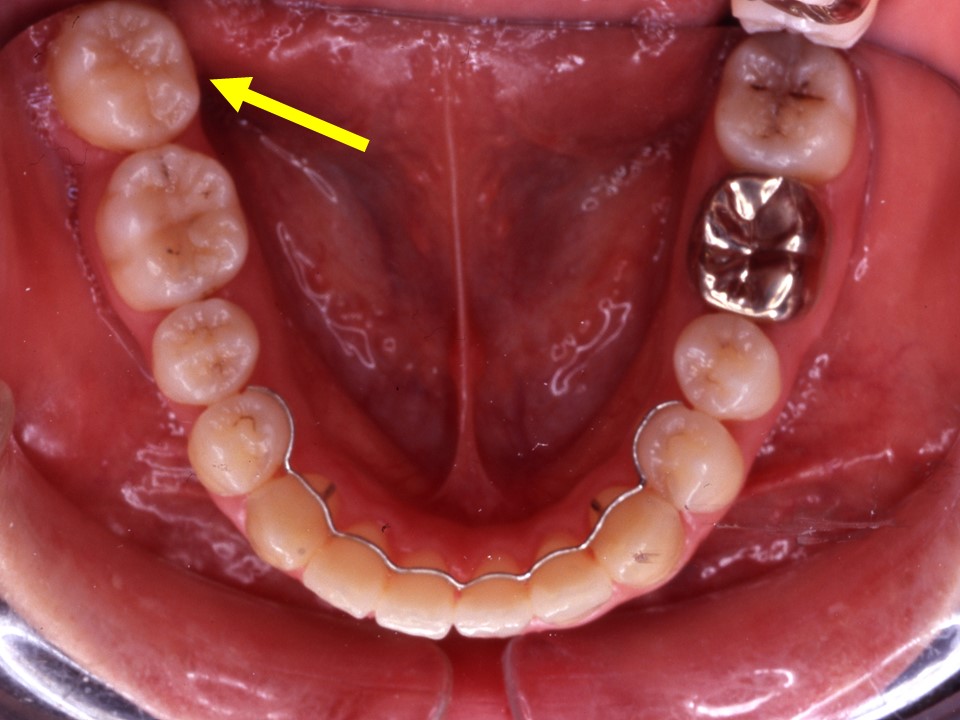

上顎大臼歯頬側転移

スペース不足で外側に並んだ第二小臼歯 あき歯科医院の医院ブログ